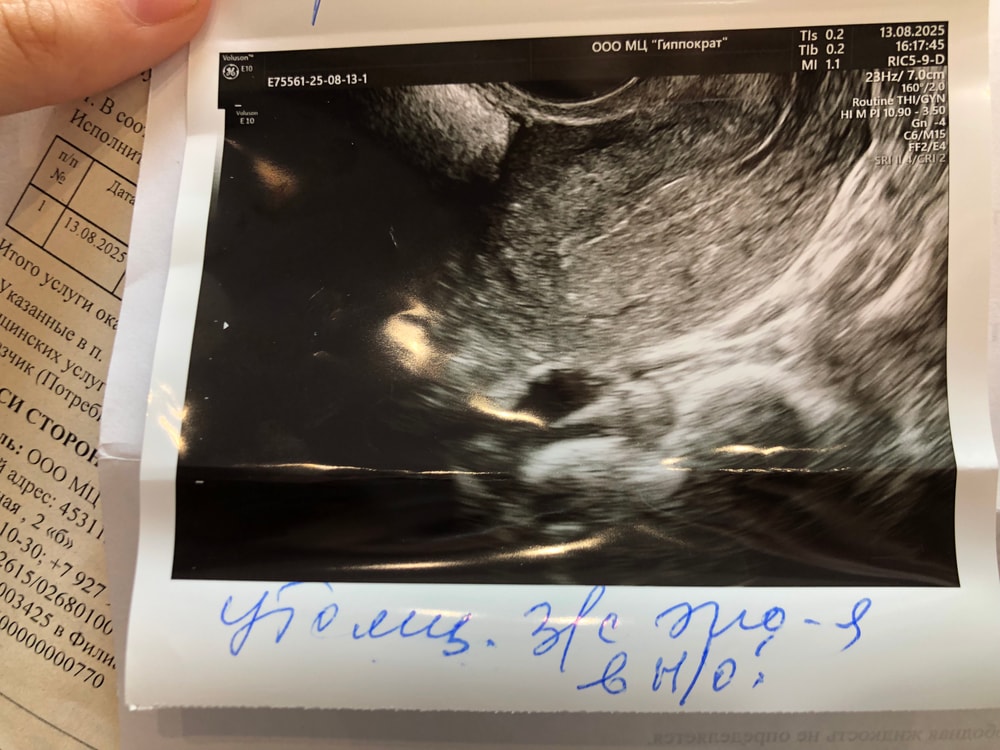

Задолбалась с этим эндометрием, 2 месяца назад была операция, так опять неоднородный эндометрий

Алиса → Зачатие УЗИ планирую беременность Рязань Что скажете по поводу такой картины Задолбалась с этим эндометрием, 2 месяца назад была операция, так опять неоднородный эндометрий Посмотрите еще 20 записей на эту тему Я уже не знаю что делать с этим эндометрием😭 Когда вы пошли на первое УЗИ после положительного теста на беременность ? Похожие записи Картины 🤗 1 дз, что скажете? По тестам 🙏🏼 Крым, лето 2025 Что скажете? Яна полюбила позировать для фото❤️ Чаты Беременных Выберите чат: Июлята-2026 Августята-2026 Сентябрята-2026 Октябрята-2026 Ноябрята-2026 Декабрята-2026